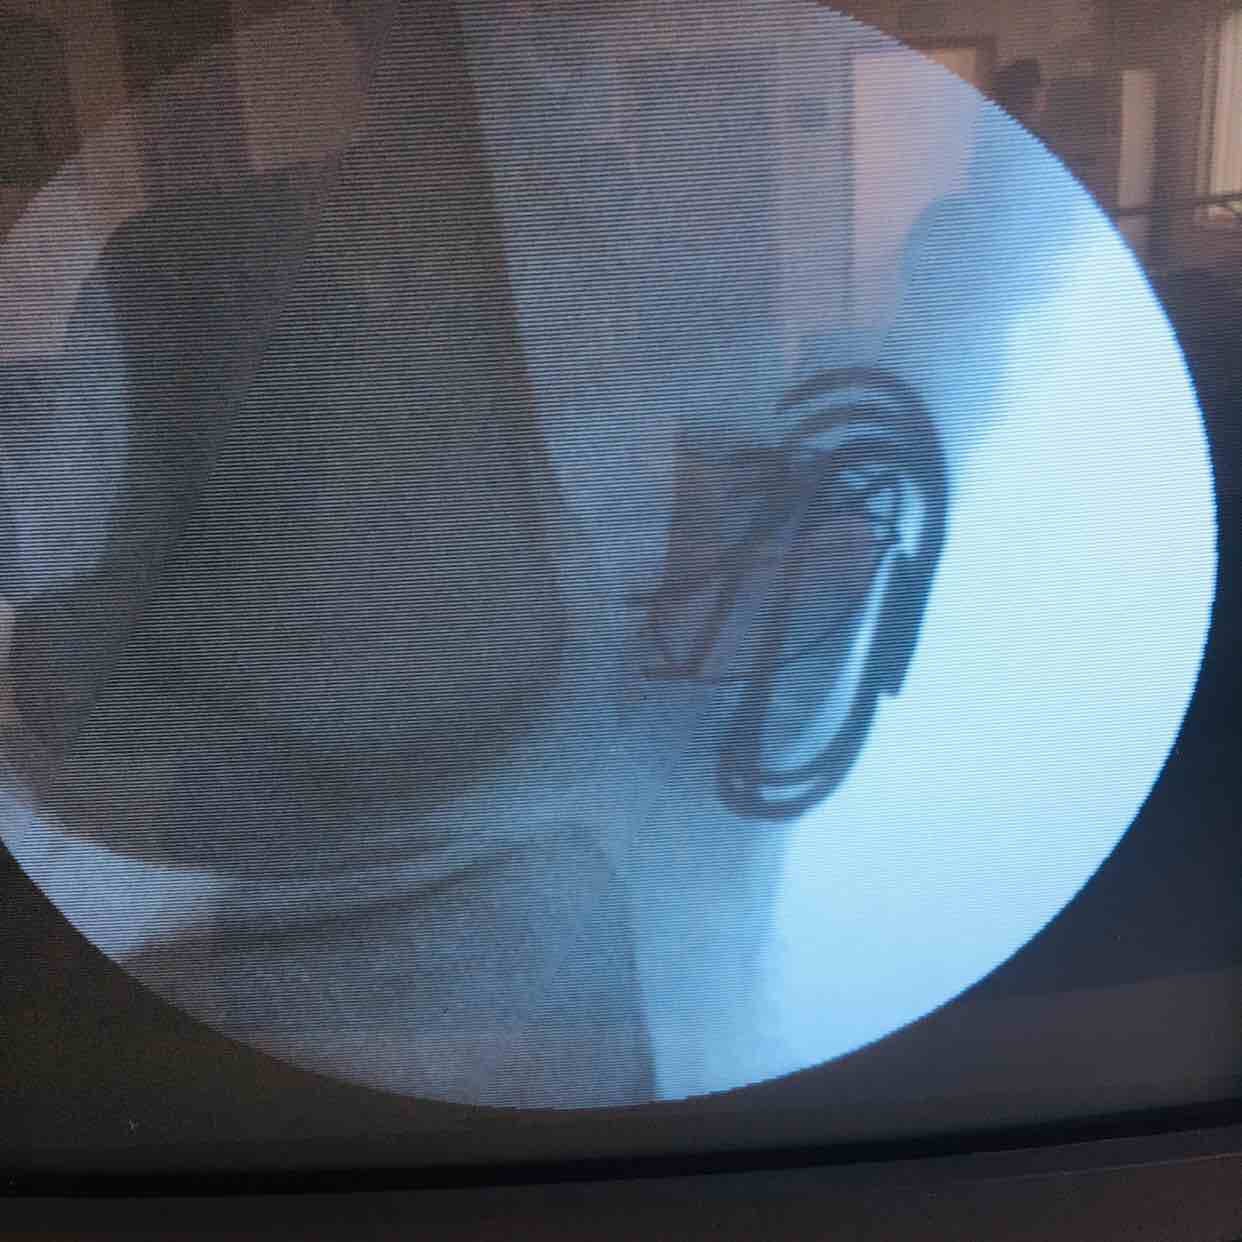

髌骨粉碎性骨折(髌骨爪➕克氏针固定)

诊断左髌骨粉碎性骨折在腰麻下行切复内固定术,术后抗炎,消肿止痛等处理。